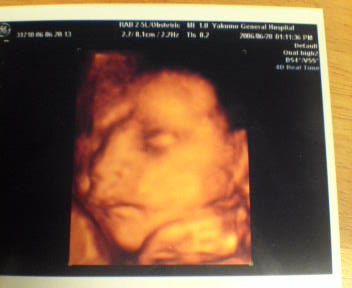

8ヶ月 胎児 エコー-Jan 19, 21 · 妊娠7週6日(妊娠2ヶ月)のエコー写真 妊娠7週6日のエコー検査ではキユーピー人形のような形の胎芽が確認できました。 胎芽の頭からお尻までの長さである「頭殿長(とうでんちょう)」(CRL)は151mmで、推定週数は妊娠8週0日。Aug 01, 07 · 妊娠後期 (28週目~35週目)の超音波エコー写真を紹介します。 井上裕子先生 プロフィール 東京都立川市 井上レディスクリニック院長。 産婦人科専門医、日本乳癌学会認定医、認定健康スポーツ医 他。 診療のかたわら、思春期から更年期の様々

妊娠後期(5ヶ月,6ヶ月,7ヶ月,8ヶ月,9ヶ月) > 胎児エコー画像にて胃が大きく写る 妊娠中 32歳女性/妊娠26週 T妊娠8ヶ月(妊娠28週~妊娠31週)のエコー写真 ©ママリ 妊娠8ヶ月はおなかの赤ちゃんは40cmを超え、体重も1,500gを超えてくる時期です。赤ちゃんはほとんどの器官が完成に近づき、目の網膜が完成することで明るさを感じることができるようになります。 ©ママリJan 14, · 妊娠8ヶ月(妊娠28週、29週、30週、31週)の胎児と母体の状態 妊娠28週から妊娠8ヶ月。妊娠後期に突入です。臓器は細部までも完成形に近づき、呼吸に似た運動をしたり、ウンチを作ったり、働き方を練習中。

Jan 28, 15 · 28w1dそうクリニックにてSep 12, 17 · 妊娠29週目(29w0d~6d)のエコー写真とエピソード|妊娠8ヶ月 妊娠29週目は妊娠8ヶ月第2週にあたります。 赤ちゃんの大きさは40cm前後にまで成長し、羊水も最大量となるのでママのお腹は前にせり出します。Sep 15, 17 · 妊娠32週目は、妊娠9ヶ月の第1週目です。お腹は更に大きくなり、動悸や息切れ、後期つわりやおりもの、むくみなどのトラブルに悩まされるママも増えてきます。運動不足になりがちなので、急激な体重増加には気を付けましょう。また、お腹の中で赤ちゃんの位置が決まってくるの

Sep 06, 17 · 妊娠8週目(8w0d~6d)のエコー写真とエピソード|妊娠3ヶ月 妊娠8週目は、妊娠3ヶ月の第1週目にあたり、妊娠初期と呼ばれる時期です。Aug 21, · 妊娠8ヶ月 妊娠31週エコー写真① 性別は男の子とわかってるんですがはっきりと見えたのでエコー写真にしてくれました。笑 妊娠8ヶ月 妊娠31週エコー写真② 横顔の写真です。目玉と眼球までみえますねーと言われました。妊娠4週になると見えてくる、「胎嚢」「卵黄嚢」って何? 妊娠5週になると脳や神経、心臓など臓器、それに手足や目、耳の原型もできるってホント? 妊娠6~7週で、心臓の動き出す!? まだ「胎児」と呼んでもらえない妊娠2ヶ月の「胎芽」時代の赤ちゃんのこと、母体のこと。

妊娠28週目 28w0d 6d のエコー写真とエピソード 妊娠8ヶ月 Cozre コズレ 子育てマガジン